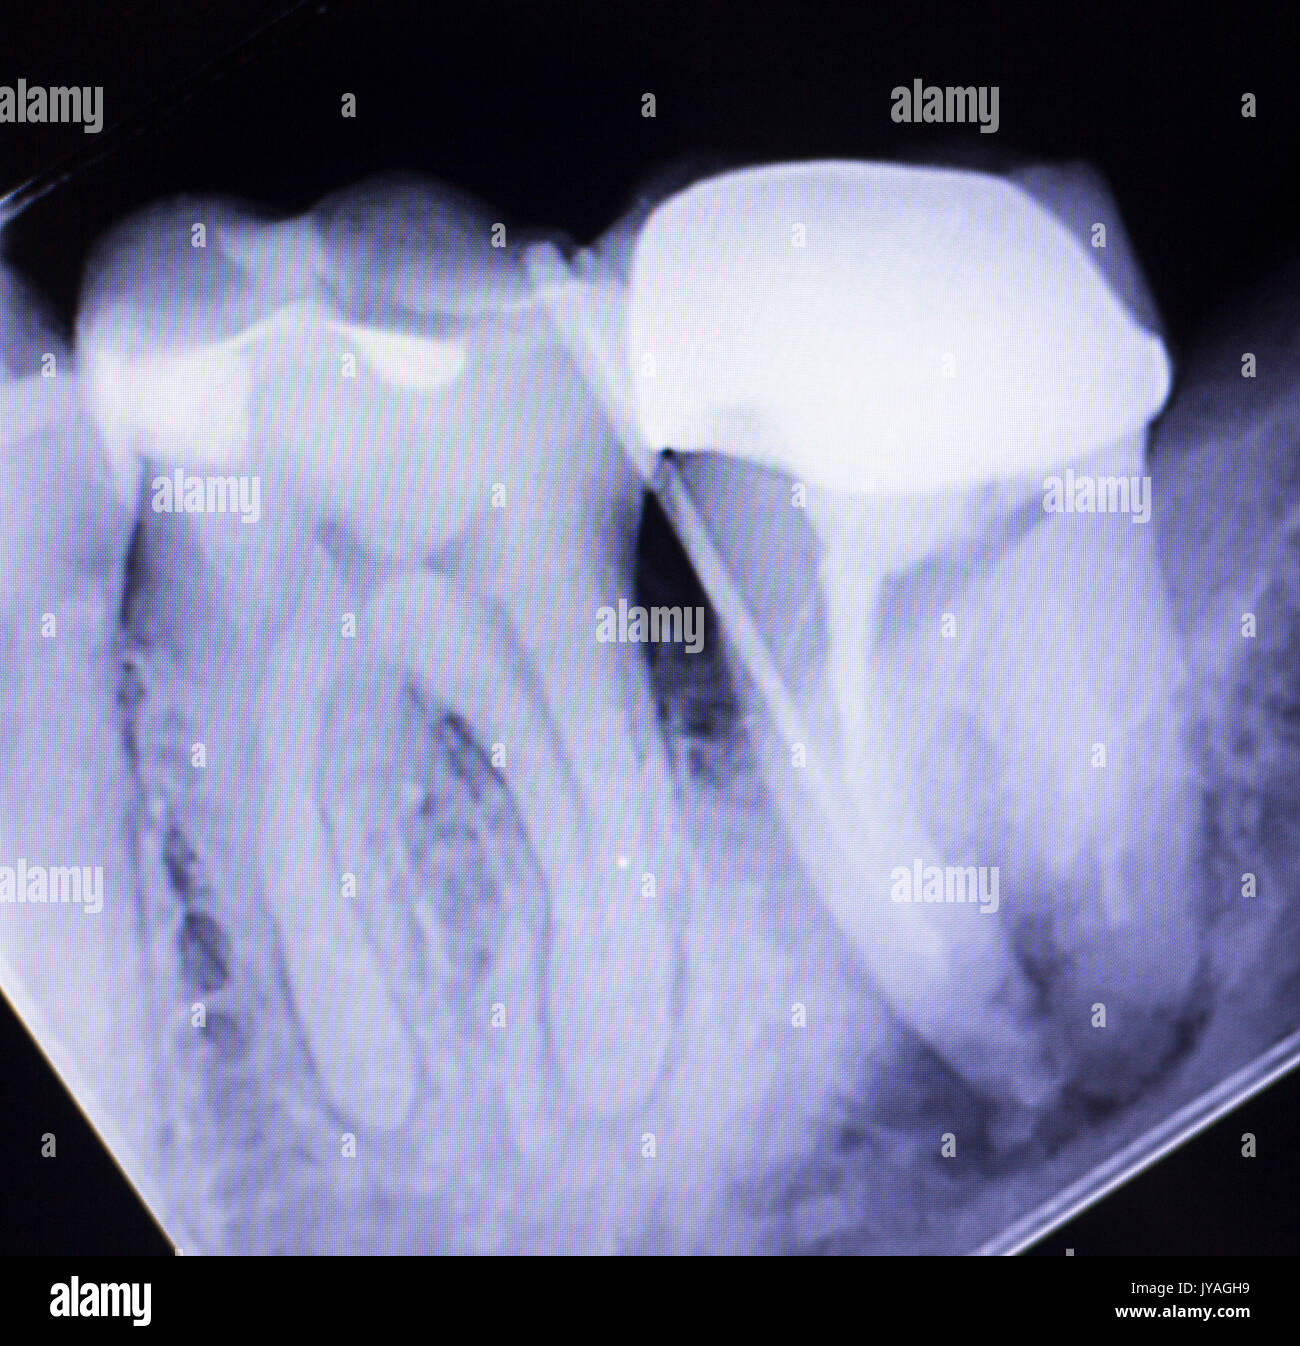

From www.alamy.com

Dental xray test scan of tooth with crown filling and root canal Can You See Tooth Infection On Xray However, if a tooth infection has spread beyond the. tooth infections can be sneaky; The answer is not always straightforward. Often, there are no visible symptoms until they progress. dental (periapical) abscesses are an acute infection of the periapical tissue around the root of the tooth. Unfortunately, they have limited field of view and. Can You See Tooth Infection On Xray.

Dental xray test scan of tooth with crown filling and root canal Can You See Tooth Infection On Xray However, if a tooth infection has spread beyond the. Unfortunately, they have limited field of view and. Often, there are no visible symptoms until they progress. The answer is not always straightforward. tooth infections can be sneaky; dental (periapical) abscesses are an acute infection of the periapical tissue around the root of the tooth. Can You See Tooth Infection On Xray.